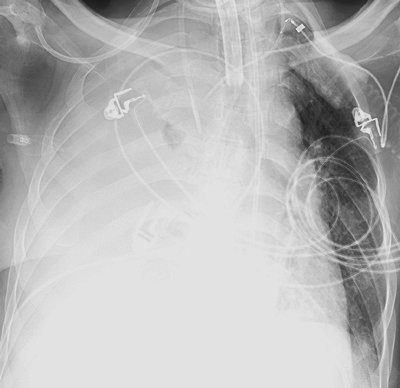

FIGURE 11-1. Left lung collapse. Anteroposterior (AP) chest radiograph shows the tip of the endotracheal tube (arrow) in the right main bronchus, resulting in collapse of the left lung. The left hemithorax is completely opaque and the mediastinum is shifted to the left.